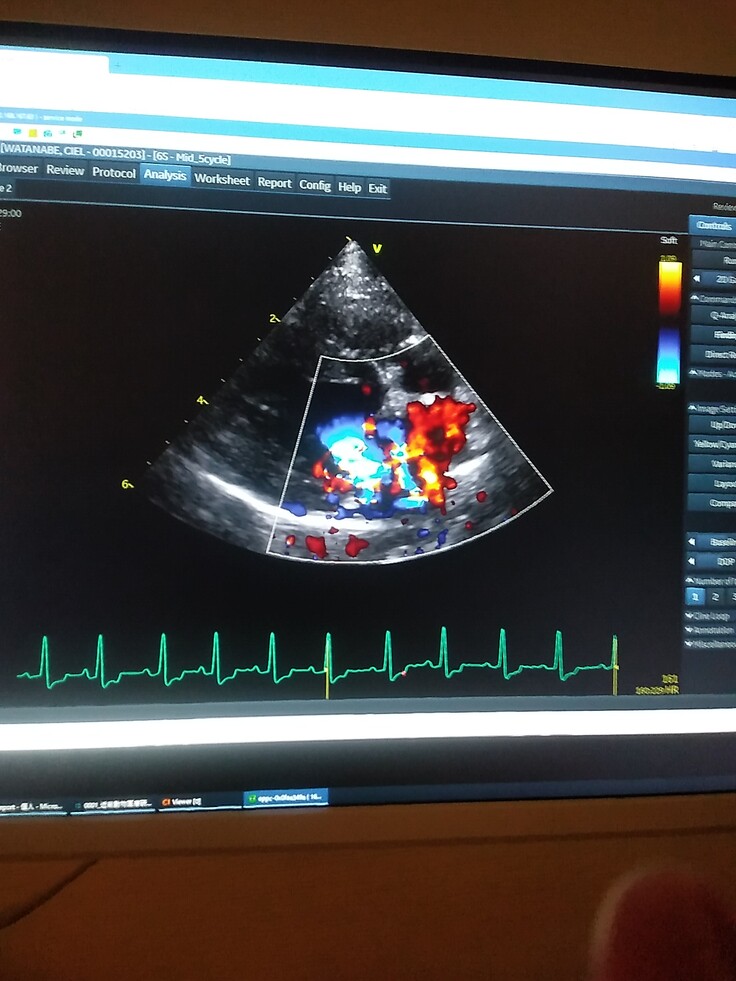

Cielの弁膜はブチブチに切れている状態で、かなり逆流もある。

※血液が逆流しています。

※3月9日、二次診療で獣医師から検査結果を説明して頂きました。